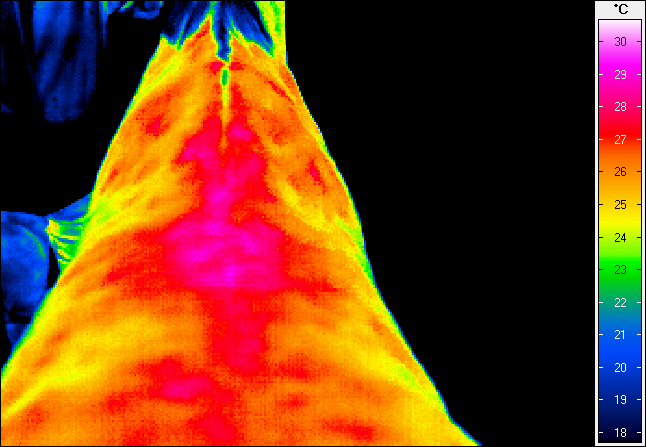

Termografia umożliwia nieinwazyjny pomiar rozkładu temperatury na powierzchni ciała konia. Wynikiem badania jest obraz – termogram, w którym poszczególne barwy odpowiadają określonym zakresom temperatur. Uzyskany rozkład cieplny odzwierciedla przede wszystkim ukrwienie tkanek powierzchownych, aktywność metaboliczną mięśni oraz właściwości izolacyjne skóry i okrywy włosowej.

W warunkach prawidłowych rozkład temperatury ciała konia charakteryzuje się wysokim stopniem symetrii pomiędzy lewą i prawą stroną. Najwyższe wartości temperatur obserwuje się w okolicach dobrze unaczynionych, takich jak oczy, nozdrza czy większe masy mięśniowe, natomiast najchłodniejsze obszary obejmują dalsze odcinki kończyn. Odstępstwa od tego wzorca – zwłaszcza asymetrie przekraczające około 1°C – mogą wskazywać na zaburzenia fizjologiczne lub rozwijające się procesy zapalne.

Metoda ta pozwala na identyfikację obszarów o podwyższonej temperaturze, związanych z zapaleniem ścięgien, więzadeł, torebek stawowych czy okostnej, często jeszcze przed pojawieniem się wyraźnych objawów klinicznych. Oprócz kończyn, istotnym obszarem zastosowania termografii jest grzbiet konia. Zaburzenia w obrębie mięśni przykręgosłupowych, więzadeł nad- i międzykolcowych czy stawu biodrowo-krzyżowego często mają charakter złożony i nie zawsze są łatwe do jednoznacznego rozpoznania przy użyciu standardowych metod. Termografia umożliwia wizualizację zmian w aktywności cieplnej tych struktur, co może wskazywać miejsca przeciążenia, bólu lub kompensacji ruchowych.